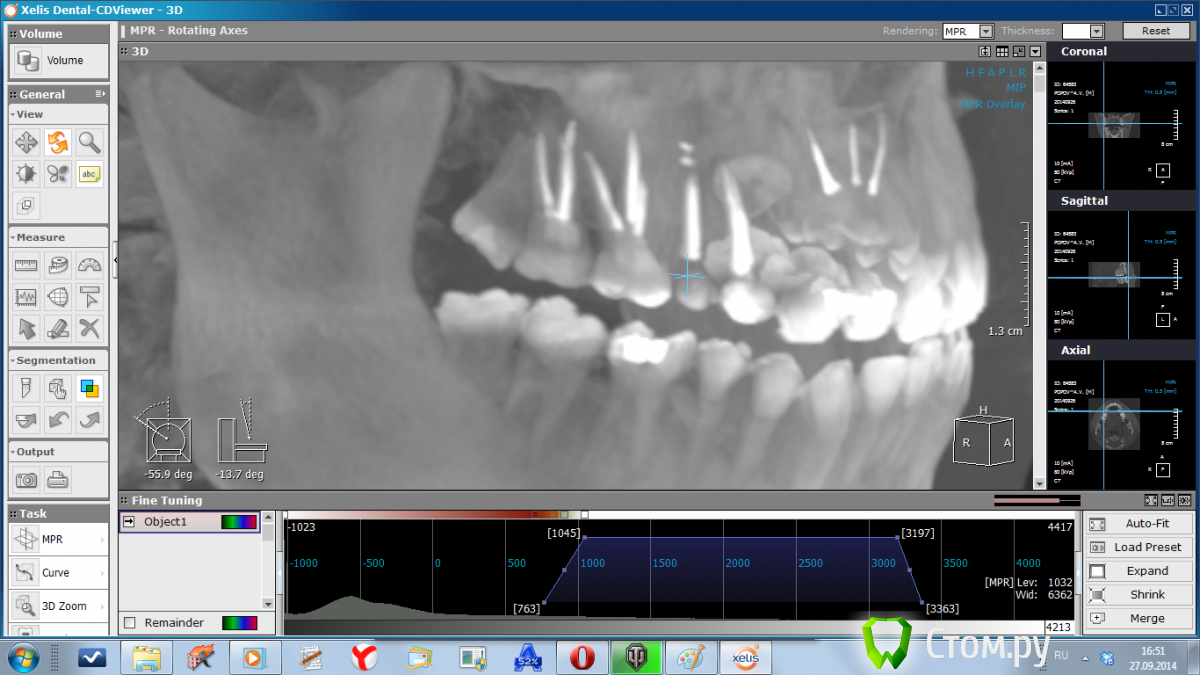

WHEELSS Опубликовано 30 сентября, 2014 Поделиться Опубликовано 30 сентября, 2014 (изменено) Здравствуйте, посмотрите пожауйста снимки сделанные из КТ. Интересует зуб верхняя правая пятерка (с одним корнем). Как запломбирован канал? Нет ли кисты?Зуб болит каждый день, уже на протяжении двух месяцев. Изменено 30 сентября, 2014 пользователем WHEELSS Ссылка на комментарий

dr-krasnov Опубликовано 30 сентября, 2014 Поделиться Опубликовано 30 сентября, 2014 Зуб запломбирован с выведением пломбировочного материала за пределы апикального отверстия, один из фрагментов находится, судя по всему, в толще слизистой оболочки верхнечелюстного синуса, что вызывает воспаление и может объяснить ваши симптомы. 1 1 Ссылка на комментарий

SDC Опубликовано 1 октября, 2014 Поделиться Опубликовано 1 октября, 2014 (изменено) Дайте, пожалуйста, срезы КТ в трансверсальной (горизонтальной) проекции. А еще лучше - выложите zip-папку Data (c .dcm файлами) на облако и дайте ссылку на скачивание.Скачал, открыл. Вижу одну единственную маленькую причину, которая сначала привела к остаточному пульпиту, а сейчас к хр. периодонтиту. (если, конечно, мы рассматриваем 15 зуб, как единственный причинный) Это доп.канал, расположенный палатинально. очень часто анатомия верхний 5-х зубов именно такова: один магистральный канал, который в апикальной части расходится на 2, "ласточкин хвост". Срез в апикальной части корня, где контурируется 2 слившихся корня, намекает на подобную анатомию.Это предположение получит подтверждение при:1. Наличии чувствительности на холодное и/или горячее в первые дни после эндолечения 15 зуба. (из анамнеза)2. Положительной динамике после повторной обработки канала.3. При визуализации бокового (палатинального) ответвления магистрального канала в микроскоп. http://s017.radikal.ru/i432/1410/b0/89dec2d707be.jpghttp://s019.radikal.ru/i624/1410/12/8beb2b221607.jpghttp://s009.radikal.ru/i308/1410/a2/22f792e49f66.jpg Изменено 1 октября, 2014 пользователем SDC 1 1 Ссылка на комментарий